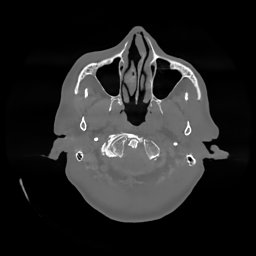

III-D Real Clinical Data Experiment

The experimental results on clinical head data are shown in Fig. 4. The reference images were reconstructed using the fast iterative shrinkage-thresholding algorithm (FISTA) with total variation regularization from non-truncated projection data. In the WCE reconstructions (Fig. 4(b)), severe truncation prevents accurate recovery of anatomical structures outside the FOV. Despite being trained solely on simulated data with a domain gap, all deep learning models can restore a substantial portion of the missing anatomy. Among them, the diffusion-based methods recover soft-tissue boundaries more faithfully than the conventional deep learning approach FBPConvNet, highlighting their stronger image generation capability. However, cDDPM reconstructions exhibit more noticeable noise than those from other methods, consistent with the simulated data results. The patchDiffusion model introduces artifacts within the FOV, likely due to its patch-wise processing strategy. While I2SB shares the same limitations as other diffusion models in perfectly restoring soft-tissue detail, it produces fewer residual noise patterns and fewer artifacts within the FOV boundaries. Overall, Fig. 4 demonstrates the strong efficacy of I2SB in reconstructing real CBCT data.